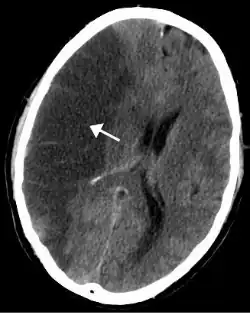

Le diagnosi di TIA e di ictus sono diagnosi cliniche. Tuttavia la tomografia computerizzata (TC) e la risonanza magnetica (RM) senza mezzo di contrasto sono utili per escludere patologie che possono mimare l'ictus e permettono di documentare la presenza di una lesione, la natura ischemica di questa, la sua sede ed estensione, la congruità con la sintomatologia clinica.

Imaging neuroradiologico

La TC è l'esame di prima istanza da eseguire in corso di ischemia acuta in quanto tecnica rapida, ampiamente disponibile e in grado di fornire tutte le informazioni necessarie: escludere alcuni "stroke mimickers", individuare la presenza di emorragie (differenziando quindi l'ictus ischemico da quello emorragico) e riconoscere i segni precoci di ischemia, che precluderebbero la possibilità di effettuare un trombolitico medico o interventistico.